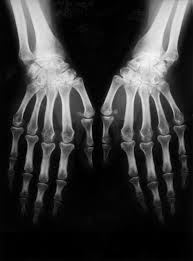

Baricitinib successful in arthritis phase 3 study | Courtesy of moosealmighty.com

Incyte Corp. and Eli Lilly and Company recently announced that its investigational medicine baricitinib proved superior to the placebo that was used in the Phase 3 trial study for rheumatoid arthritis (RA).

The study was specifically designed to find treatments for patients with moderate to severe rheumatoid arthritis. These patients previously showed such a low response or such a high intolerance of the traditional conventional disease-modifying antirheumatic drug that new treatment needed to be developed. Included in the study were 684 such patients.

"Despite treatment advances, many people with RA continue to experience active disease, including pain, joint stiffness, disability and progressive joint damage," Incyte Corp. chief drug development and medical officer Rich Levy said. "These results suggest that baricitinib could provide an additional treatment option for patients who are not responding to conventional drugs."